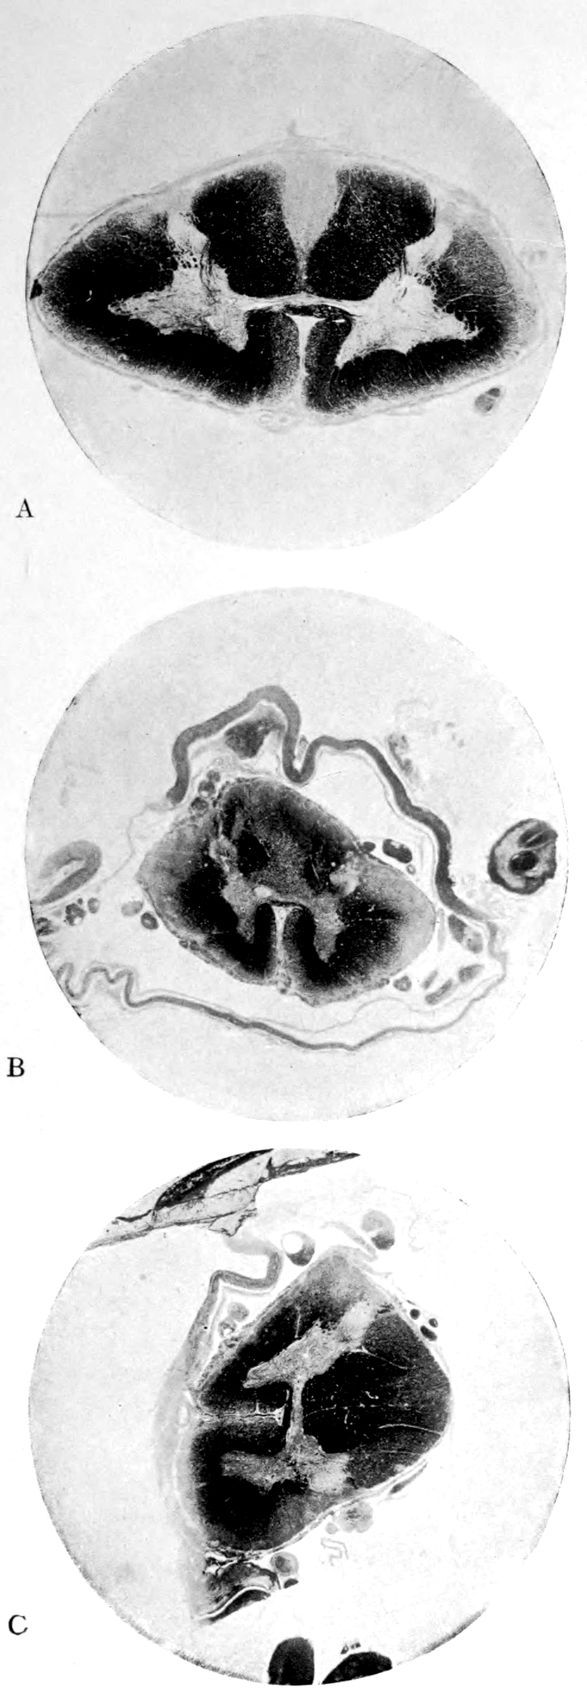

Case I. Spinal Cord (Three Levels) Showing:

A. Marginal sclerosis—effect of old meningitis now extinct.

B. Posterior column sclerosis—effect of meningitis about posterior roots also now extinct.

C. Bilateral pyramidal tract sclerosis—effect of cerebral thrombotic lesions.

Note distortion of tissues in B and C, partly artificial (tissues in places diffluent).

Vascular neurosyphilis—effects of syphilitic thrombosis of Sylvian artery 10 years before death. (Case 4.)

Case 4. (See previous figure for brain lesion.) Three levels of the spinal cord showing unilateral pyramidal tract sclerosis, 10 years after cerebral thrombosis.